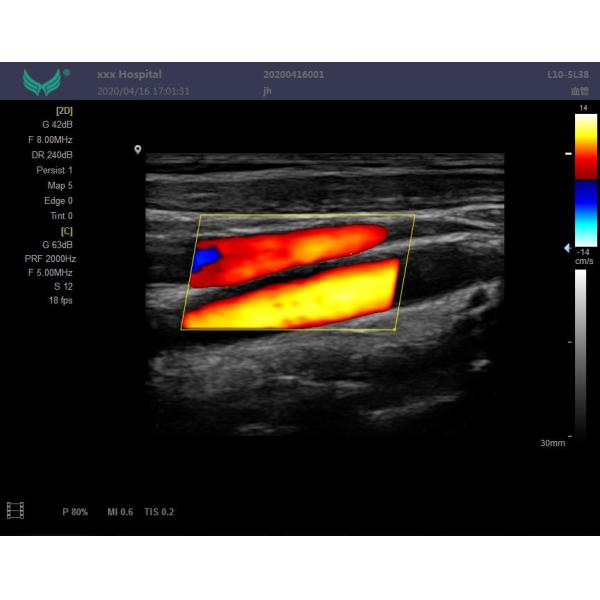

Imaging Mode : M Mode ,B Mode ,Cfm,Pdi,Pw

Class II Abdominal Scan Portable Ultrasound Machine PW CFM PDI Mode

High End Color Doppler Diagnostic System Doppler Ultrasound Machine

E80 Portable Ultrasound Color Doppler Diagnostic Scanner

XF3800 (E80) color doppler ultrasound system applications include abdomen, obstetrics, gynecology, blood vessels, small organs, urology,neonates and pediatrics. Includes scanning modes such as B / CFM / PDI / PW / CW / M and provides excellent resolution and sensitivity. Support convex array probe, linear array probe, convex probe, cavity probe, phased array probe, 4D probe. Integrated network ultrasound workstation, support for DICOM transmission. Using embedded computing system, the system is safe, stable and high-speed operation into one.The XF3800 is a value choice beyond your expectation!

--Display mode: B,B/B,M,B/M,CFM,CMF/B,PDI,B/PW,CW etc mode;